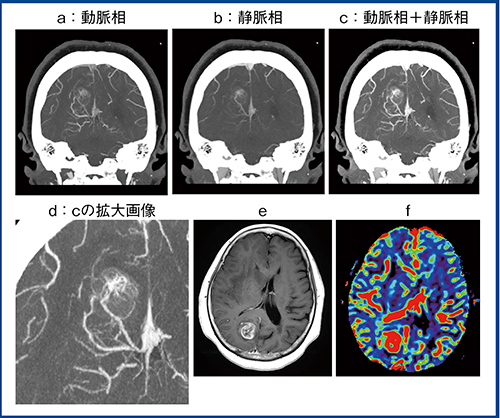

図4は,右後頭頭頂葉付近にできた悪性神経膠腫(high grade glioma)の症例で,Aquilion Precisionで撮影した動脈相(a),静脈相(b)と,動脈相と静脈相を足し算(スタック)した画像(c)である。cを拡大表示(d)すると,後大脳動脈(PCA)の分枝から病変部に向かって流入する栄養血管と,腫瘍内部のhypervascularな部分が明瞭に観察できる。病変部は造影MRI(e)でも強調され,MR灌流画像(f)の脳血流量(CBV)も高値を示しているが,従来,血管造影でなければ得られなかった情報が超高精細CTで評価できるメリットは大きい。

図4 悪性神経膠腫(high grade glioma)の比較画像

a〜d:Aquilion Precision

e:造影MRI f:MR灌流画像(CBV)